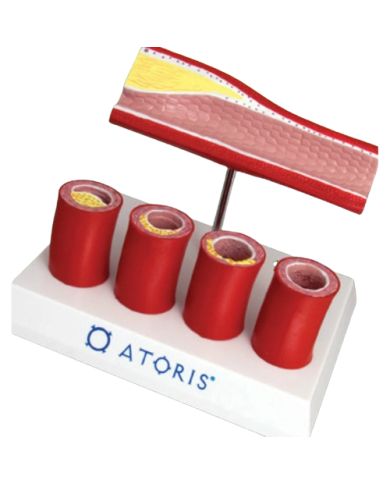

Modello anatomico PER FORNITURE CASE FARMACEUTICHE

Modello anatomico PER FORNITURE CASE FARMACEUTICHE

Modello anatomico PER FORNITURE CASE FARMACEUTICHE

Modello anatomico PER FORNITURE CASE FARMACEUTICHE

Modello anatomico PER FORNITURE CASE FARMACEUTICHE

Modello anatomico PER FORNITURE CASE FARMACEUTICHE

Modello anatomico PER FORNITURE CASE FARMACEUTICHE

Modello anatomico PER FORNITURE CASE FARMACEUTICHE

Modello anatomico PER FORNITURE CASE FARMACEUTICHE

Modello anatomico PER FORNITURE CASE FARMACEUTICHE

Modello anatomico PER FORNITURE CASE FARMACEUTICHE

Modello anatomico PER FORNITURE CASE FARMACEUTICHE

Modello anatomico PER FORNITURE CASE FARMACEUTICHE

Modello anatomico PER FORNITURE CASE FARMACEUTICHE

Modello anatomico PER FORNITURE CASE FARMACEUTICHE

Modello anatomico PER FORNITURE CASE FARMACEUTICHE

Modello anatomico PER FORNITURE CASE FARMACEUTICHE

Modello anatomico PER FORNITURE CASE FARMACEUTICHE

Modello anatomico PER FORNITURE CASE FARMACEUTICHE

Modello anatomico PER FORNITURE CASE FARMACEUTICHE

Modello anatomico PER FORNITURE CASE FARMACEUTICHE

Modello anatomico PER FORNITURE CASE FARMACEUTICHE